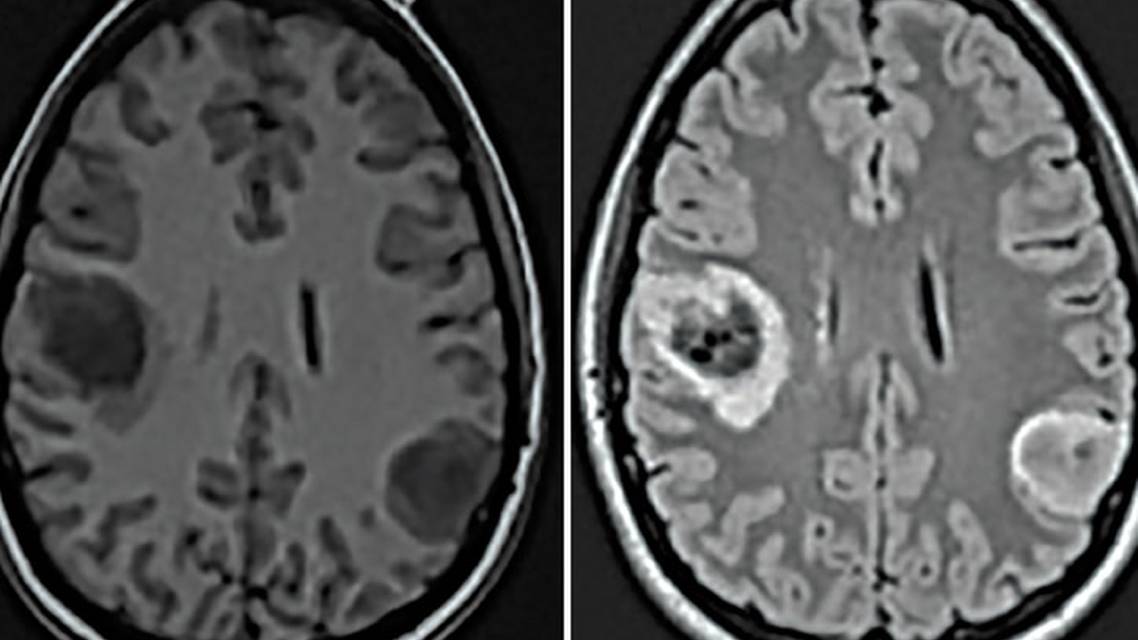

LB, a right-handed woman age 29 and 10 weeks pregnant, presented to a local hospital with a new-onset focal-to-bilateral tonic-clonic seizure described as clonic movements of her left face and arm that secondarily progressed to a convulsion. LB had never had symptoms before this presentation, and her neurologic examination at admission had no focal findings. Out of concerns for potential fetal harm from gadolinium-based contrast, a brain MRI without contrast was performed and showed 2 lesions (Figure). The larger lesion was a right posterior frontal mass measuring 3.3x3.0x2.7 cm, and the second lesion was in the left inferior parietal lobe and measured 2.2x3.0x2.4 cm. LB was treated with lamotrigine 25 mg; however, she experienced several focal seizures over the following week.